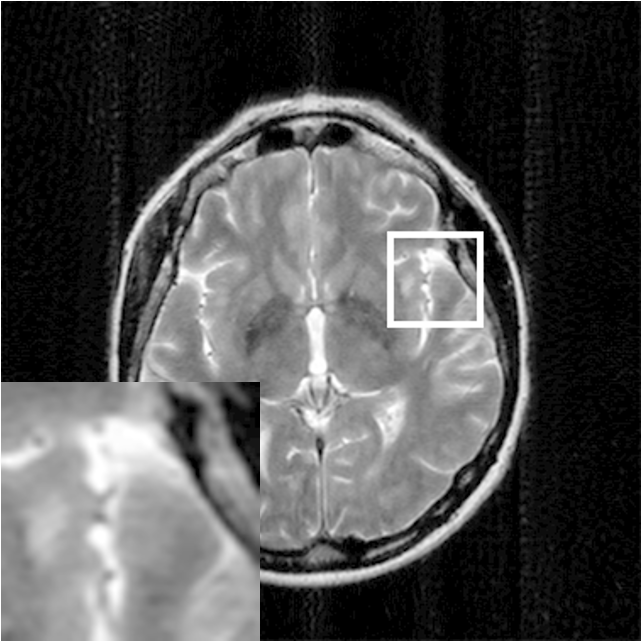

Where x is denoted as the MRI to be reconstructed, y are the k-space data, and Fusubscript𝐹𝑢{F_{u}} represents the under-sampled Fourier encoding matrix. The first term Fuxy22superscriptsubscriptnormsubscript𝐹𝑢xy22{\|{F_{u}}\emph{x}-\emph{y}\|}_{2}^{2} indicates data fidelity that can ensure the consistence between the Fourier coefficients of the reconstructed image and measured data. The second term Risubscript𝑅𝑖{R_{i}} is an analytical, sparsifying transform term, and αisubscript𝛼𝑖{\alpha_{i}} is a factor for balancing data fidelity and transform terms. MR images can be generated by inverse Fourier transform of the sampled k-space data, which are the Fourier coefficient of an object. However, aliasing artifacts (noise-like) are produced by the incoherence of under-sampled k-space in transform domain, as shown in Fig. 1.

Figure 1: The zero-filled reconstruction. (a) is a full-sampled MRI, (b) is a 20% radial sampling mask, (c) is the zero-filled reconstruction under (b), and (d) is the reconstruction using our method. Note that aliasing artifacts are clearly seen in the zero-filled reconstruction (c), which impair diagnostic information. However, our algorithm can remove these unpleasant artifacts (d).